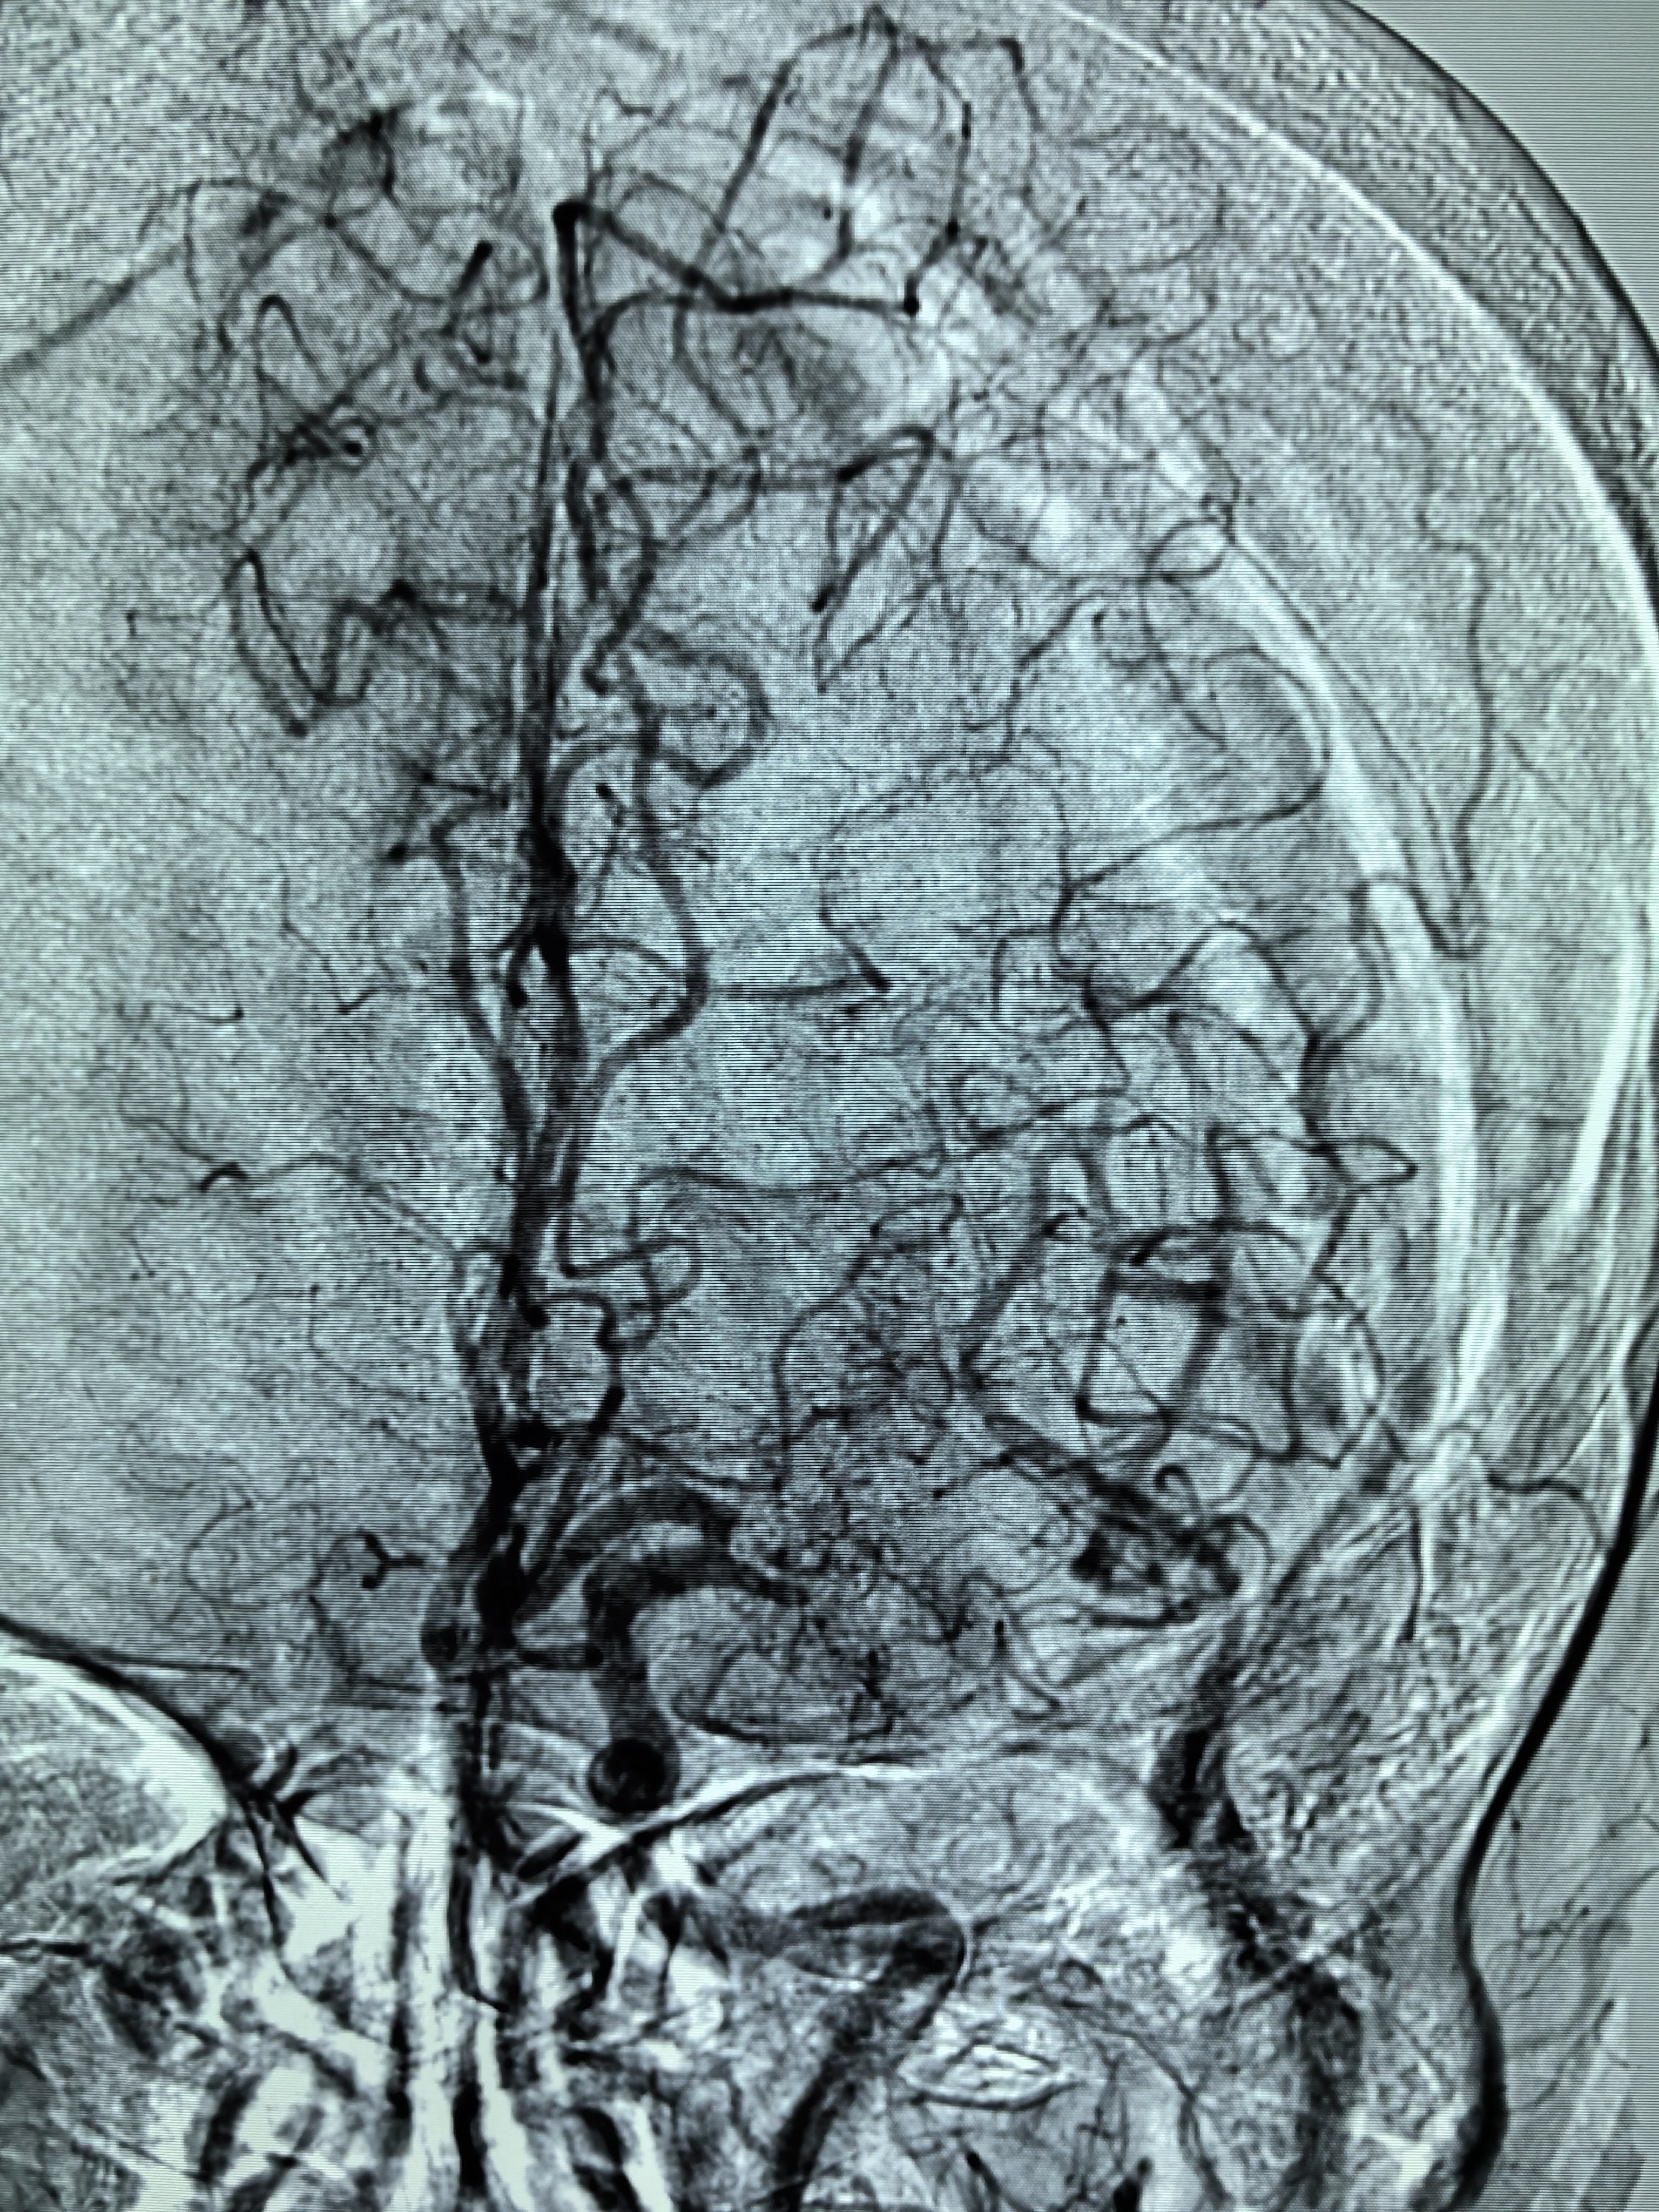

1、本例患者老年女性,系骨科术后次日醒后卒中,经核磁评估提示左侧大脑中动脉闭塞,系责任血管,患者心电图示房颤,考虑心源性栓塞可能性大。

2、本例患者SWIM技术取栓一次后血管再通,颅内血流通畅。